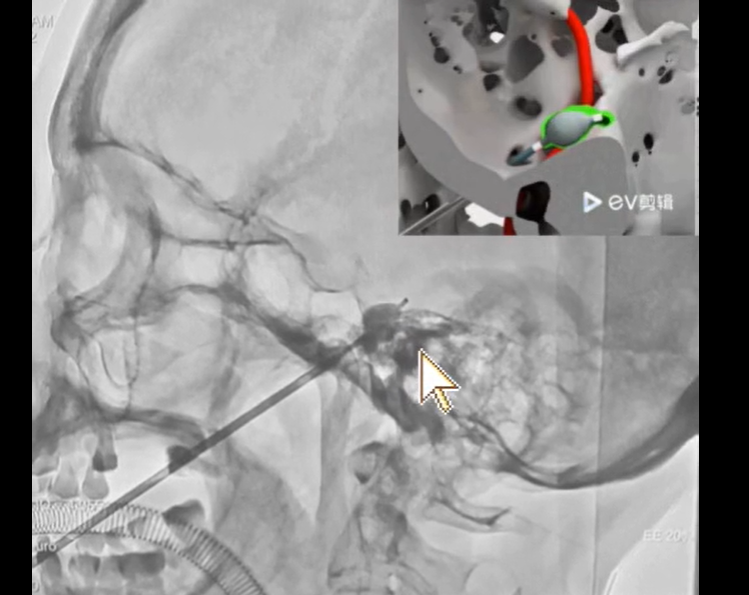

1. 穿刺定位:局部麻醉,Hartel前入路法,C臂透视实时引导。

2. 卵圆孔捕捉:避开棘孔、破裂孔、颈内动脉等"危险邻居"。

3. 球囊的“梨型舞蹈”:"梨形"提示球囊位于Meckel腔内,未突入后颅窝压迫脑干。可最佳性的压迫痛觉纤维,保留触觉纤维。

4. 压迫参数控制:充盈0.6ml造影剂,平衡疗效与神经损伤程度压迫3min。